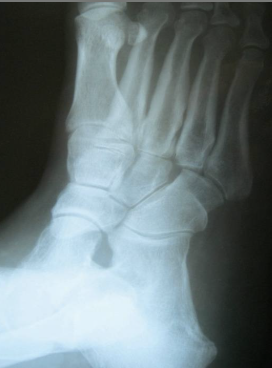

There is no gold standard concerning diagnostic testing for pathology in this area. Plain film radiographs may note medial subluxation of the fourth metatarsal on the cuboid, which can represent the presence of hypermobility. Radiographs in combination with computed tomography (CT) scans may also demonstrate degenerative changes at those respective joints. A technetium-99m magnesium diphosphonate (MDP) bone scan may show uptake in the soft tissue angiogram phase, representing increased blood flow and thus inflammation secondary to hypermobility. If osteoarthritis is present, one will see focality at the bone phase. Magnetic resonance imaging (MRI) may also indicate marrow edema, primarily at the cuboid on the T2 (water) images.4